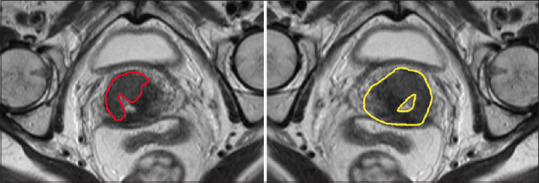

Methods: This study included 99 patients with pathologically confirmed cervical cancer who underwent an MRI prior to receiving brachytherapy. The GTV and HR-CTV were delineated on T2-weighted MRI and inputted into 3D Slicer for radiomic analysis. Before feature extraction, all images were preprocessed to a combination of several parameters of Laplacian of Gaussian (1 and 2), resampling (0.5 and 1), and bin width (5, 10, 25, and 50). The reproducibility of radiomic features was analyzed using the intra-class correlation coefficient (ICC).